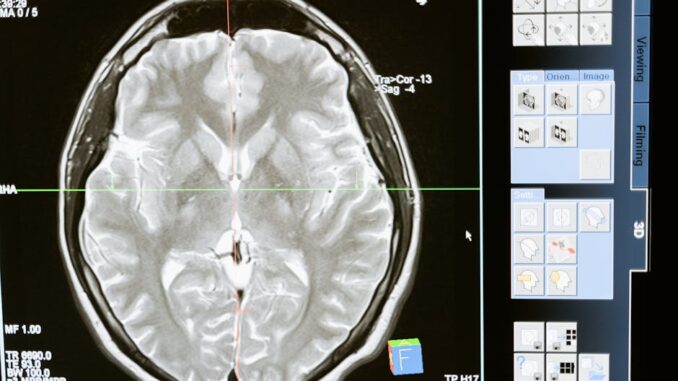

Medical imaging stands as an indispensable cornerstone of contemporary healthcare, furnishing clinicians with critical visual insights essential for the precise diagnosis, staging, and monitoring of a vast spectrum of medical conditions. From the early days of X-rays to today’s sophisticated computed tomography (CT), magnetic resonance imaging (MRI), positron emission tomography (PET), and ultrasound, these technologies have continually evolved, pushing the boundaries of non-invasive diagnostics. The sheer volume and complexity of the data generated by these modalities, however, present significant challenges for human interpretation, often requiring specialized expertise and considerable time. In recent years, the advent and rapid maturation of deep learning, a powerful branch of machine learning inspired by the structure and function of the human brain’s neural networks, has ushered in a new era for medical imaging. This technological paradigm shift offers sophisticated tools capable of analyzing intricate imaging data with an accuracy and efficiency that was previously unattainable, fundamentally redefining the capabilities of computer-aided diagnosis and analysis.

• Brain Tumor Detection and Delineation: CNNs, including advanced U-Net variants, have been extensively employed to segment brain tumors (gliomas, meningiomas) from multi-sequence magnetic resonance imaging (MRI) scans, such as T1-weighted, T1-weighted with contrast enhancement (T1Gd), T2-weighted, and Fluid-Attenuated Inversion Recovery (FLAIR) images. These models can delineate different sub-regions of a tumor (e.g., enhancing tumor, necrotic core, edema) with high accuracy, assisting neurosurgeons in pre-operative planning and oncologists in assessing treatment response. For instance, studies have shown deep learning models achieving Dice scores exceeding 0.85 for whole tumor segmentation in the BraTS (Brain Tumor Segmentation) challenges, significantly outperforming many traditional methods (ajesjournal.org).